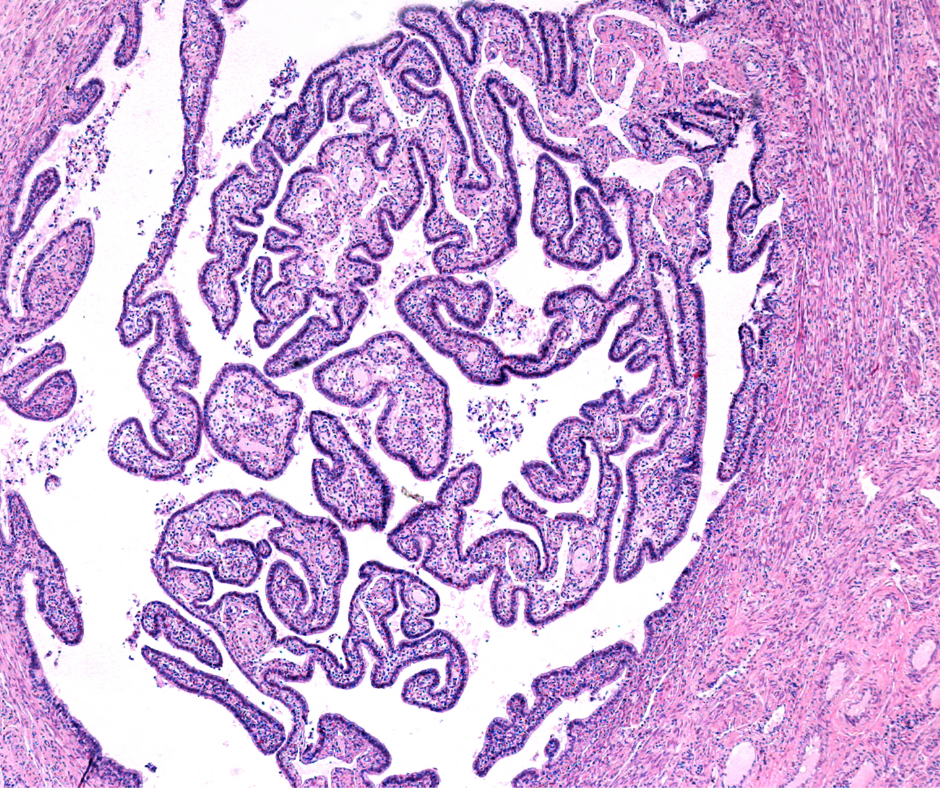

Selective salpingography may provide enhanced assessment of fallopian tubes and fallopian tube recanalization could be a viable alternative to facilitate natural conception, according to new research from the Department of Radiology at the University of Briti…

The combination of selective salpingography to assess fallopian tubes and subsequent fallopian tube recanalization by an interventional radiologist could represent a significant advance for women wit… [+2156 chars]